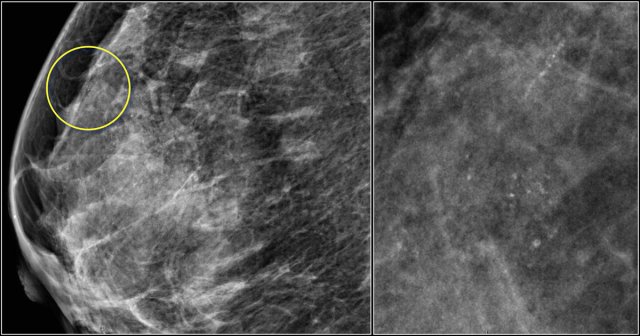

Here an example of a focal asymmetry seen on MLO and CC-view.

Local compression views and ultrasound did not show any mass.